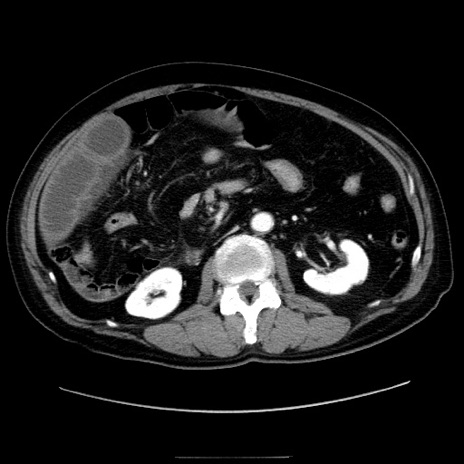

症例30(横断像)

【症例】80歳代男性

【主訴】臍周囲痛

【現病歴】約6時間前から臍下部痛が出現。次第に腹部膨隆・背部痛も生じてきたため来院。背部痛の場所は変化しない。

【身体所見】意識清明、BT 36.3℃、BP  131/87mmHg、P 87bpm、SpO2 100%(RA)、臍周囲自発痛・圧痛あり、反跳痛なし、自発痛部位に一致して板状硬あり、腹部膨隆、腸雑音減弱、CVA tenderness両側陰性。